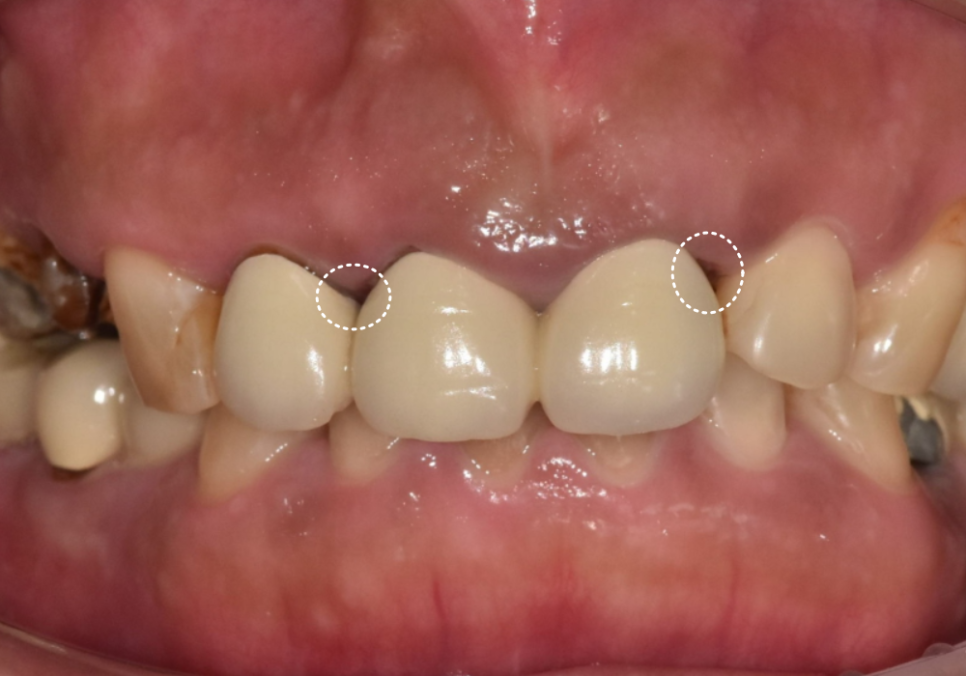

251223

입안을 살펴보니...

브릿지 경계 라인이 조금 까맣게 비쳐보이고

잇몸도 꽤 부어있는 걸 확인할 수 있었습니다.

방사선 상, 보철 경계 부위가

까맣게 나타나는 것을 보아

아무래도 2차 충치의 가능성이 높아

브릿지를 제거해보기로 했습니다.